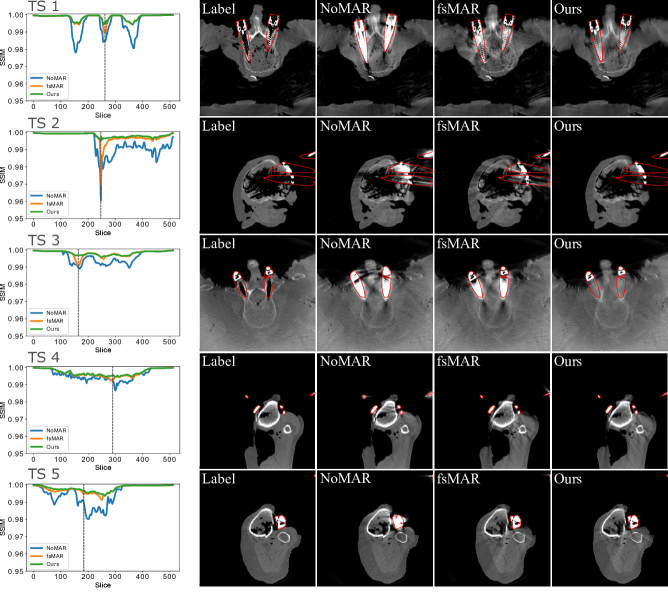

Figure 8: Overview about the per-slice SSIM scores and one slice (marked as a gray dotted line) of each of the corresponding reconstructions for the first 5 TS of the first fold. Each row comprises the quantitative (left) and qualitative (right) results of one test scan. The 1st column of the qualitative results shows the label reconstructions, the 2nd column shows the reconstructions without the use of a MAR method (NoMAR), the 3rd column shows the reconstruction using the standard fsMAR method and the 4th column shows the corresponding reconstruction of using our proposed segmentation method for the modified fsMAR (Ours). The red outlines represent the envelope of the joint segmentation masks which are used to mask the metrics’ scores. All regions inside the denoted envelope are set to 00 during the metric calculations. All shown reconstructions are windowed with [500, 2048] HU.

Refer to caption

Figure 9: Overview about the per-slice SSIM scores and one slice (marked as a gray dotted line) of each of the corresponding reconstructions for the last 6 TS of the first fold. The layout and annotations are equivalent to those of Fig. 8.

By examining the qualitative results and the corresponding SSIM line plots presented in Fig. 8 illustrating the results for test scans 1 to 5 and Fig. 9 illustrating the results for test scans 6 to 11 of the first fold, similar effects can be observed. It becomes apparent that for the majority of test cases the standard fsMAR, as well as the modified fsMAR, perform equally well, with a slight beneficial tendency for the proposed approach. The differences are that marginal, that they do not visually show up in the corresponding presented slices (cf. Fig. 8 & Fig. 9). This especially holds for scans comprising knees. However, investigating the qualitative results for test scans 2, 3 (Fig. 8), 6, 8, 9 (Fig. 9) and the example in Fig. 10, significant differences can be observed. In Fig. 8 at test scan 3 comprising a spine, it can be seen that the standard fsMAR is not able to segment the complete inserted pedicle screws, but only the associated heads. Due to that, only artifacts originating from the screws’ heads are reduced, whereas present beam hardening artifacts at the tips of the screws remain unchanged. In opposition to that, the proposed approach shows reduced artifacts throughout the complete size of the screws. Similar effects can be observed for test scans 8 and 9 in Fig. 9 where the segmentation of the standard fsMAR misses parts of the screws. For test scan 2 (Fig. 8) it becomes apparent that the streak artifacts, which originate from parts of K-wires, which lie outside the FoV of the reconstruction, are reduced more efficiently using the proposed segmentation approach. The represented slice for test scan 6 (Fig. 9) shows a similar case in which metal reaches from outside the FoV into the reconstruction. Whereas the standard fsMAR is able to fully segment the present metal plate and only an insufficient part of the metal lying outside and at the border of the volume, the modified fsMAR segments all present metal parts, thus achieving a more artifact reduced reconstruction. For both cases, a significant performance difference can also be seen in the corresponding line plots. However, similar to the quantitative results, the most significant difference between the two approaches can be seen for the presented test scan in Fig. 10. While for the shown slice, the standard fsMAR is not able to reduce any of the artifacts due to a failed segmentation, our approach nearly completely removes the present artifacts. Furthermore, the superior performance is not only reached in the single presented slice but rather holds for the complete set of slices.